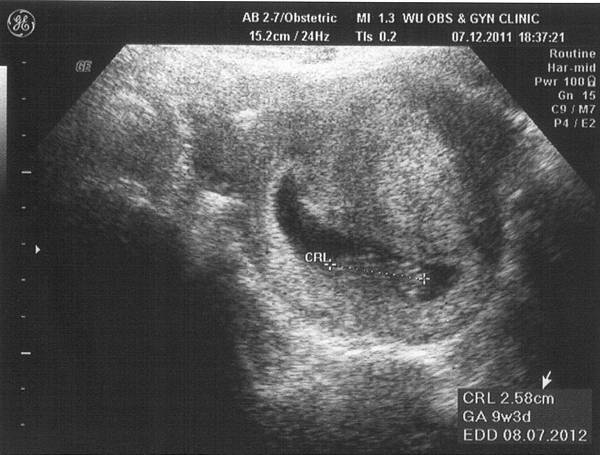

過年後最期待的就是產檢了,

我已經等不及想看寶寶啦(扭)。

而這次還要多做個唐氏症篩檢,

我最怕的抽血又來了,